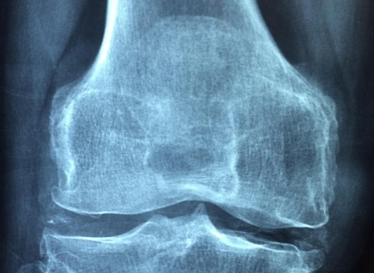

골다공증은 뼈의 밀도와 구조가 저하되어 쉽게 부러지는 만성 질환입니다. 건강한 뼈는 해면골 구조가 촘촘하고 단단하지만, 골다공증이 생기면 이 구조가 성긴 그물처럼 변해 골밀도가 급격히 낮아집니다. 결과적으로 기침, 재채기 같은 가벼운 자극에도 골절이 발생할 수 있습니다.

골다공증검사는 주로 골밀도검사(DXA)로 진행됩니다. 이 검사는 척추·대퇴골의 밀도를 수치로 확인해 골절 위험도를 평가합니다. 구봉모 교수는 “정기적인 골다공증검사는 조기 발견과 맞춤 치료의 첫걸음”이라며, “50세 이상 여성, 70세 이상 남성은 1~2년에 한 번씩 검사를 받아야 한다”고 조언합니다.